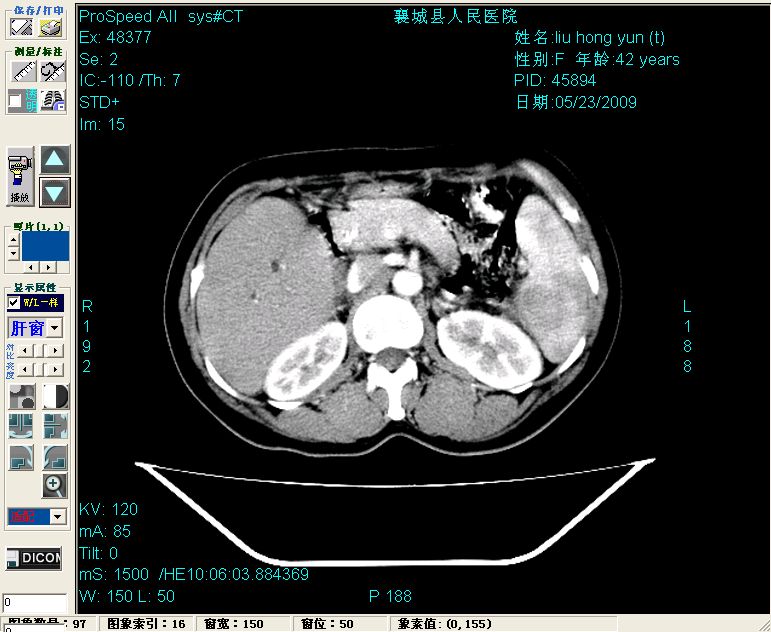

增强:

增强动脉期前述低密度区轻度早其强化,门脉期强化程度显著增高,延期扫描强化程度下降,但仍为相对高密度影

胰头部见结节状高密度影,其前方略可分辨扩强胆部管,平扫到增强始终有,但现在尚难与胃肠造影剂鉴别.

结合病史考虑,1现在引起黄疸体征的原因应该是胆总管胰段结石阻塞,建议局部胃肠造影剂排空后复查.

2左肝及右肝前叶表现考虑胆囊摘除术后所致的肝动门脉瘘形成,慢性纤维组织炎性增生.不完全除外左肝胆管细胞癌

3脾大,可能与动门脉瘘所致门脉高压有关